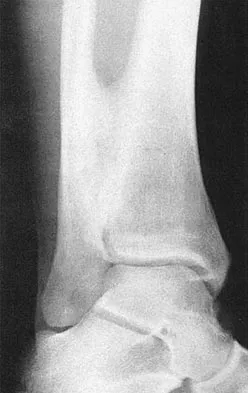

A 12-year-old boy with an ankle fracture undergoes closed reduction under sedation in the emergency department. Figure 27 shows a lateral radiograph of the ankle after two attempts at closed reduction. Based on these findings, treatment should now consist of

Explanation